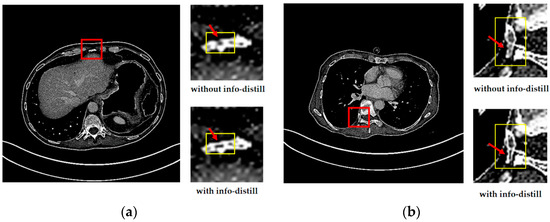

To show the reconstructed results more vividly and intuitively, we select two sets of images. We test the performance of IDMAN (with info-distill) and the model without info-distill. The reconstruction results are shown in Figure 5.

Figure 5.

The reconstructed results of IDMAN with/without information distillation. (a) A reconstructed image of clear edges; (b) A reconstructed image of accurate details.

From Figure 5a, it easy to see that the edge of the reconstructed image is broken without info-distill, while the image can restore clearer edges when the information distillation is introduced. In Figure 5b, it is obvious that more accurate details can be reconstructed when using information distillation.

It can be seen that more details can be obtained in the reconstruction results with information distillation, which also proves that our method can make better use of feature information to improve learning ability when using information distillation to extract the feature. The improvements in both the subjective visual reconstruction results and objective evaluation index show that using information distillation to make more use of feature information is effective.